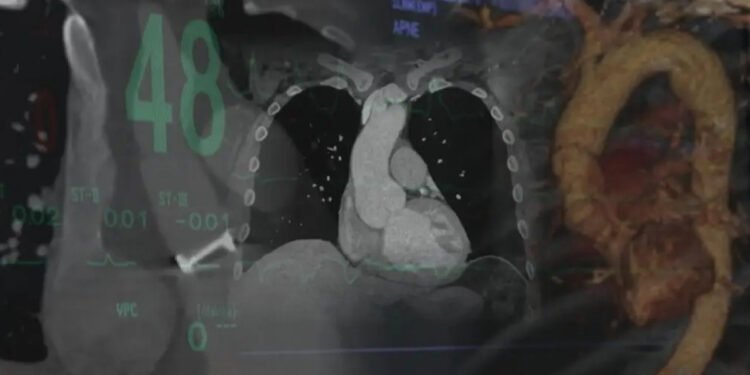

ഒട്ടാവ : ഹൃദയരോഗവുമായി ബന്ധപ്പെട്ട മാരകമായ അപകടസാധ്യതകളെക്കുറിച്ച് കാനഡയിലെ പകുതിയോളം പേർക്കും അറിവില്ലെന്ന് ഹാർട്ട് ആൻഡ് സ്ട്രോക്ക് ഫൗണ്ടേഷൻ ഓഫ് കാനഡ പുറത്തുവിട്ട പുതിയ റിപ്പോർട്ട്. ഉയർന്ന രക്തസമ്മർദവും മറ്റ് ലക്ഷണങ്ങളും അവഗണിക്കുന്നത് മരണകാരണമായേക്കാവുന്ന ഗുരുതരമായ ഹൃദയസ്തംഭനത്തിലേക്കും ശ്വാസകോശ സംബന്ധമായ അസുഖങ്ങളിലേക്കും നയിക്കുമെന്നും റിപ്പോർട്ട് മുന്നറിയിപ്പ് നൽകുന്നു. നിലവിൽ രാജ്യത്തെ 8.2 ദശലക്ഷത്തിലധികം മുതിർന്നവർ ഉയർന്ന രക്തസമ്മർദത്തിന്റെ പരിധിയിലാണെന്നാണ് കണക്കുകൾ സൂചിപ്പിക്കുന്നത്.

രോഗലക്ഷണങ്ങൾ പ്രകടമാകാതെ തന്നെ ഹൃദയത്തിലെ പ്രധാന രക്തക്കുഴലുകൾക്ക് വീക്കമുണ്ടാകുന്ന ‘അയോർട്ടിക് അന്യുരിസം’, രക്തക്കുഴലുകൾ പിളരുന്ന ‘അയോർട്ടിക് ഡിസെക്ഷൻ’ തുടങ്ങിയ അവസ്ഥകൾ പലരിലും കണ്ടുവരുന്നുണ്ട്. 38 വയസ്സുള്ള കത്രിന സിസൺ, 58 വയസ്സുള്ള ടോം ഷെർബ്ലുക്ക് എന്നിവർക്ക് അടിയന്തര ശസ്ത്രക്രിയയിലൂടെ ജീവൻ തിരിച്ചുകിട്ടിയത് ഇത്തരം അവസ്ഥകൾ തിരിച്ചറിഞ്ഞതുകൊണ്ടാണ്. 130/80 mm Hg എന്ന പരിധിക്ക് മുകളിൽ രക്തസമ്മർദം എത്തുന്നത് അപകടസാധ്യത വർധിപ്പിക്കുമെന്നും ഇത് ‘സ്ട്രോക്ക്, വൃക്കനാശം എന്നിവയ്ക്ക് കാരണമാകുമെന്നും ടൊറന്റോ സെന്റ് മൈക്കിള്സ് ആശുപത്രിയിലെ ഡോ. സുബോധ് വർമ്മ വ്യക്തമാക്കി.

ഹൃദയരോഗം എപ്പോഴും പ്രകടമായ ലക്ഷണങ്ങളോടെയല്ല വരുന്നതെന്നും പലപ്പോഴും ആദ്യ ലക്ഷണം മരണം തന്നെയായേക്കാമെന്നും ഡോക്ടർമാർ ഓർമ്മിപ്പിക്കുന്നു. കൃത്യമായ ഇടവേളകളിൽ രക്തസമ്മർദം പരിശോധിക്കുകയും കുടുംബചരിത്രത്തിൽ ഹൃദയരോഗമുള്ളവർ പ്രത്യേക ജാഗ്രത പാലിക്കുകയും വേണമെന്നും വിദഗ്ധർ നിർദേശിച്ചു.